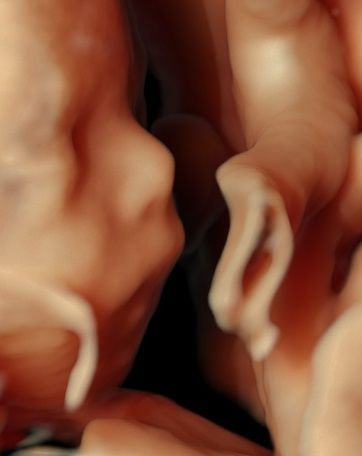

-certyfikat The Fetal Medicine Foundation (FMF) w zakresie badań prenatalnych w 11–13+6 tygodniu ciąży – przezierność karku u płodu (NT); kość nosowa u płodu (NB); przepływ w przewodzie żylnym u płodu (DV); przepływ na zastawce trójdzielnej (TR) oraz oceny ryzyka wystąpienia preeklampsji (stanu przedrzucawkowego) w ciąży.

Zdjęcia i filmy